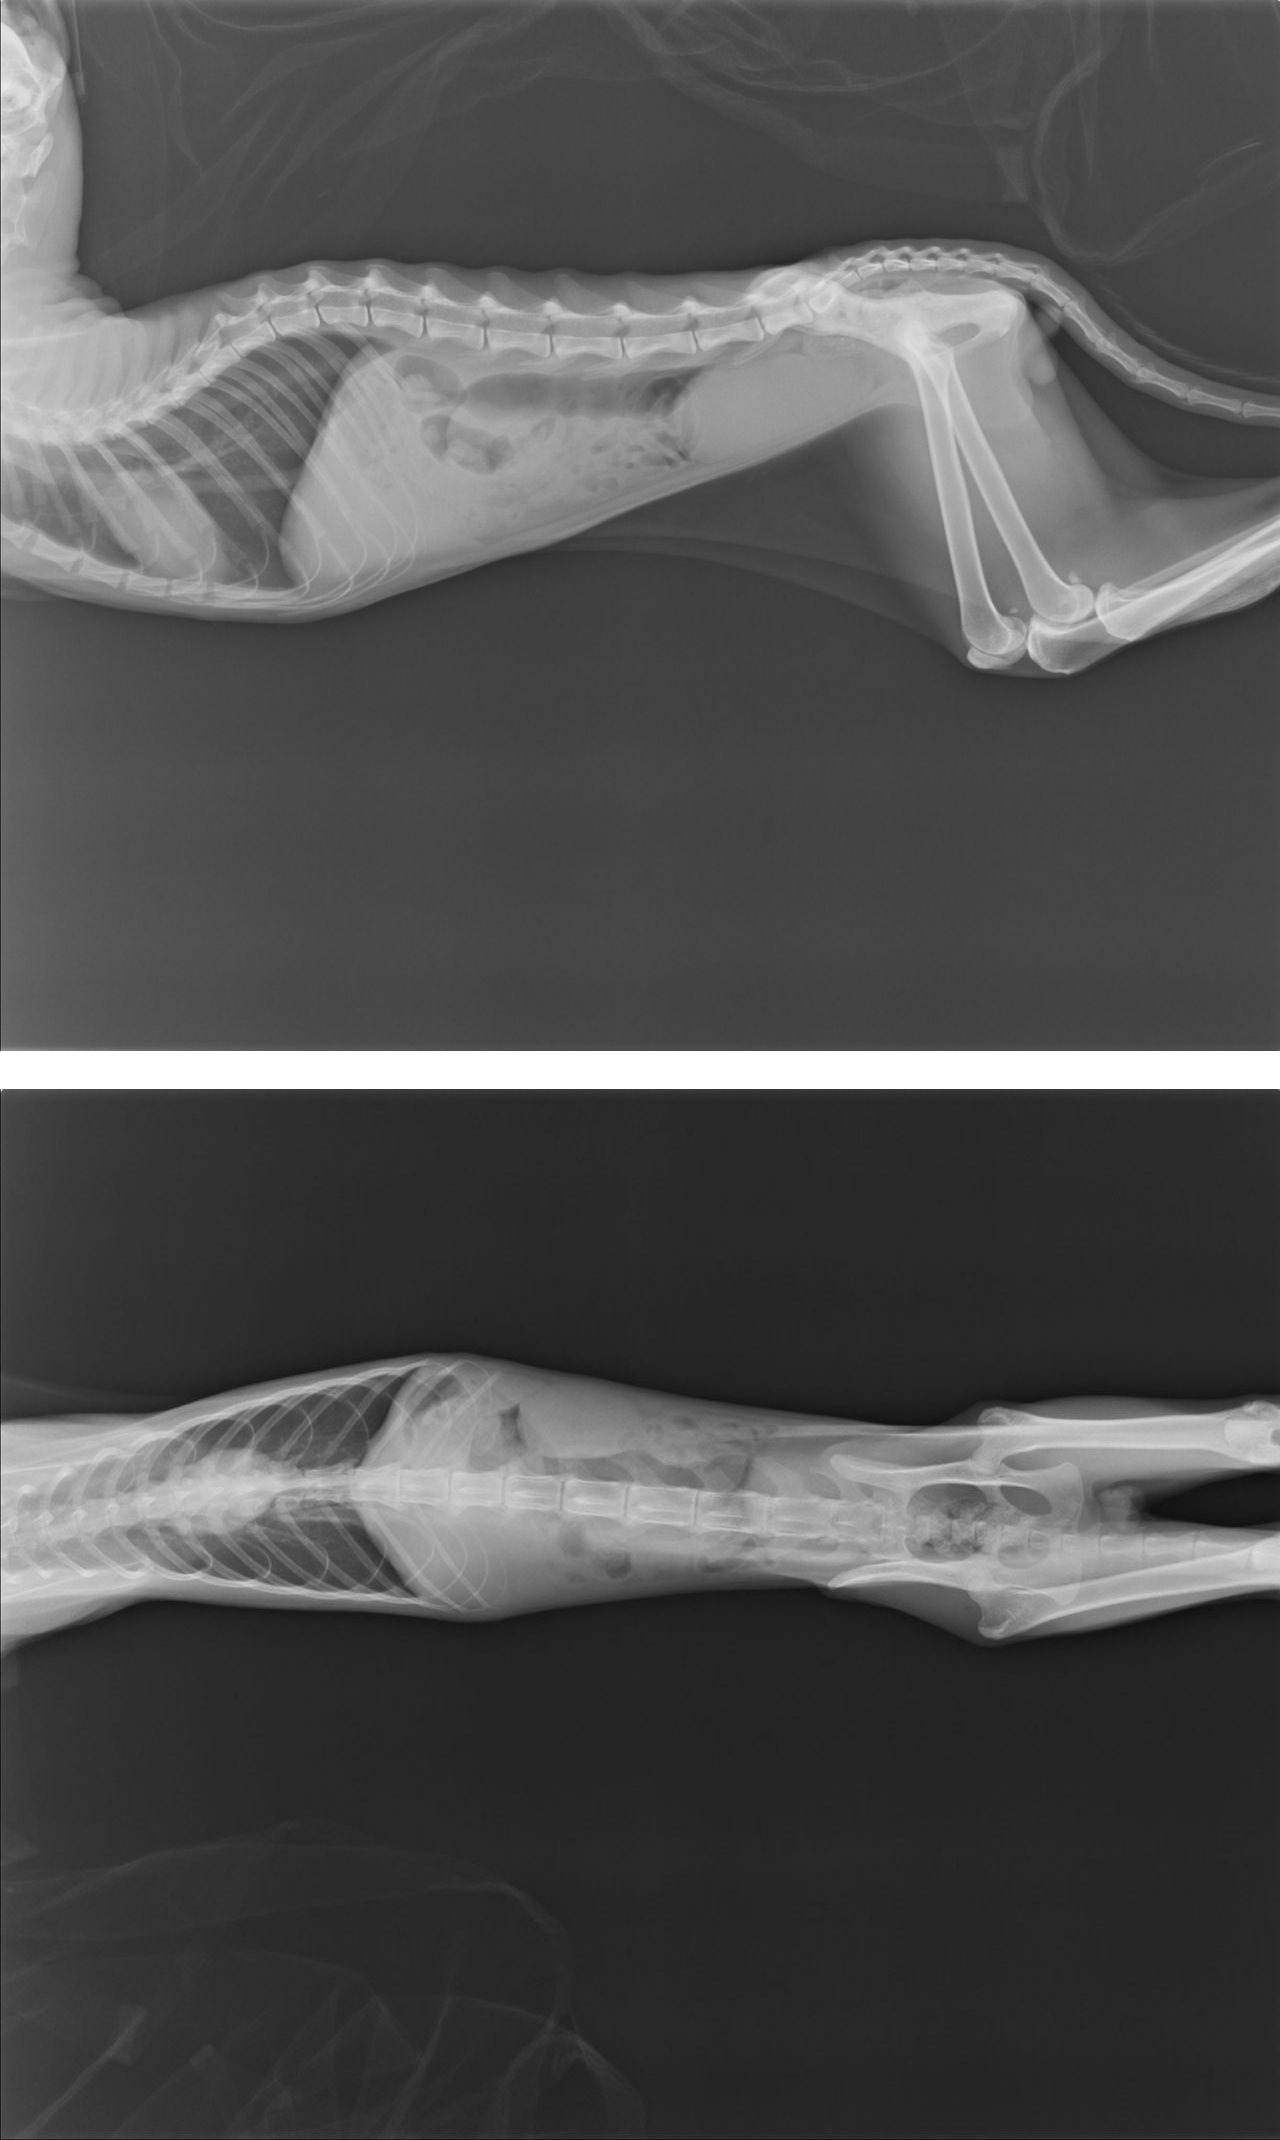

血檢檢查的狀況就是肝腎指數都偏高,白血球偏高,口腔有嚴重的潰瘍跟糜爛,

有可能是吃到什麼腐蝕性的東西或是自體免疫的口炎,x光可以看到膀胱有漲尿,

但是目前還沒看到排尿,陰莖部分有一小段有白白小結晶的影像,

醫生明天會再看看有無排尿,也可能是尿路阻塞。